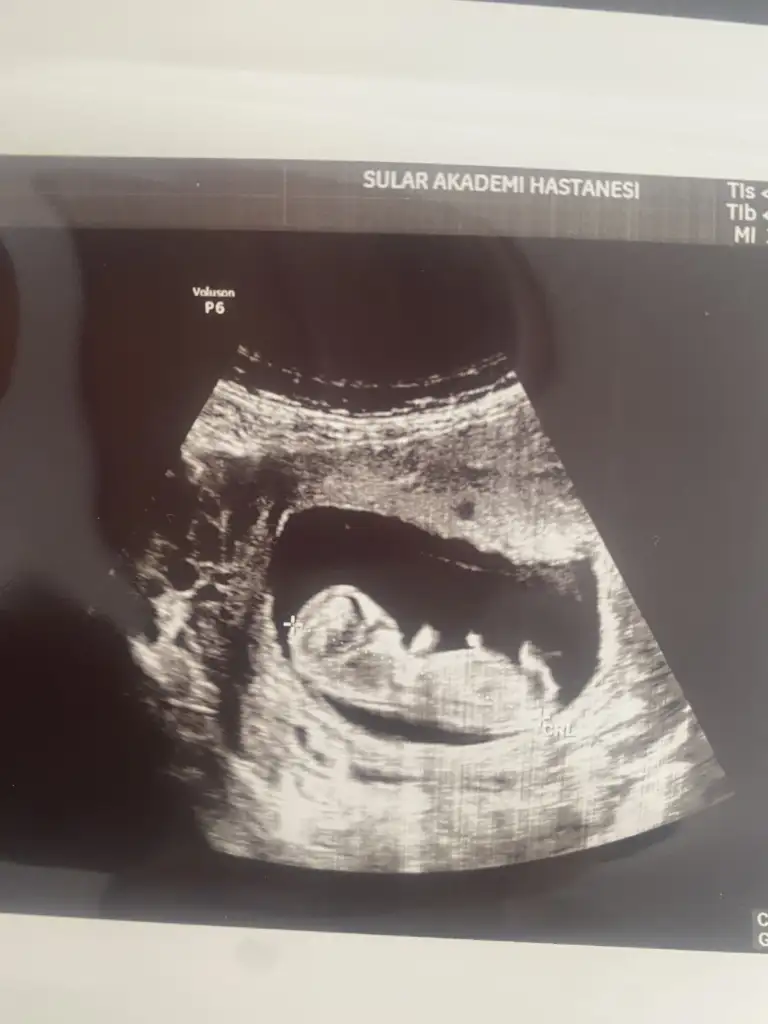

Günaydınlar bugun kontrole gittim 11 Haftalık tam. miniğim büyüyor artık bu heyecanımı sizinle paylaşmak istedim haftaya ikili tarama var cinsiyet için çook erken ama resme bakıp yorum yapabilecek var mı🙂

Eklentiler

• IMG_20250305_105324.webp

IMG_20250305_105324.webp

16 KB · Görüntüleme: 62